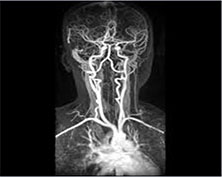

日本の脳手術は世界トップクラスの実力です。他国では手術を断られた患者さんが日本で手術を受けた結果、完治されたケースが多数あります。日本人特有の繊細な技術が大いに活かされている分野です。

脳卒中をはじめとする脳の病気は、急に症状が現れることがあるため、早期からの予防と対策が大切です。脳血管撮影、脳血管カテーテルなどの検査を定期的にすることにより早期発見をすることができます。

脳血管MRI

脳血管カテーテル